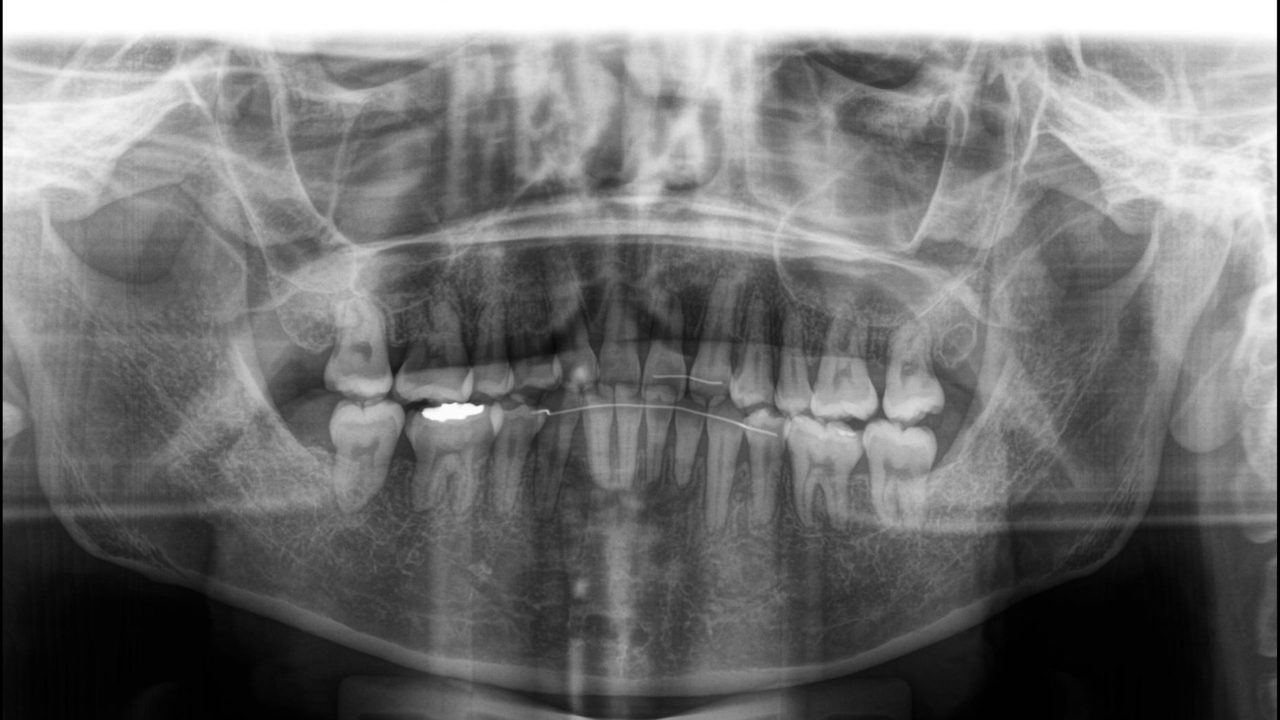

初診 レントゲン

| 備考 | 前歯の凸凹が気になるとのことでした。旦那さんも当院で矯正治療を受けていたので、奥さんもついでに治すことになりました。左上側切歯は失活しており、変色が目立つ状態でした。また、左下第1小臼歯は歯頚部に大きなむし歯があり、歯肉退縮が著しい状態でした。叢生を解消するために抜歯が必要だったので、この状態の悪い2本と右下第1小臼歯の全部で3本を抜歯することにしました。治療後は口元の印象が劇的に良化しました。 |

| 診断 | 左側アングルクラスⅠ 右側アングルクラスⅡ |